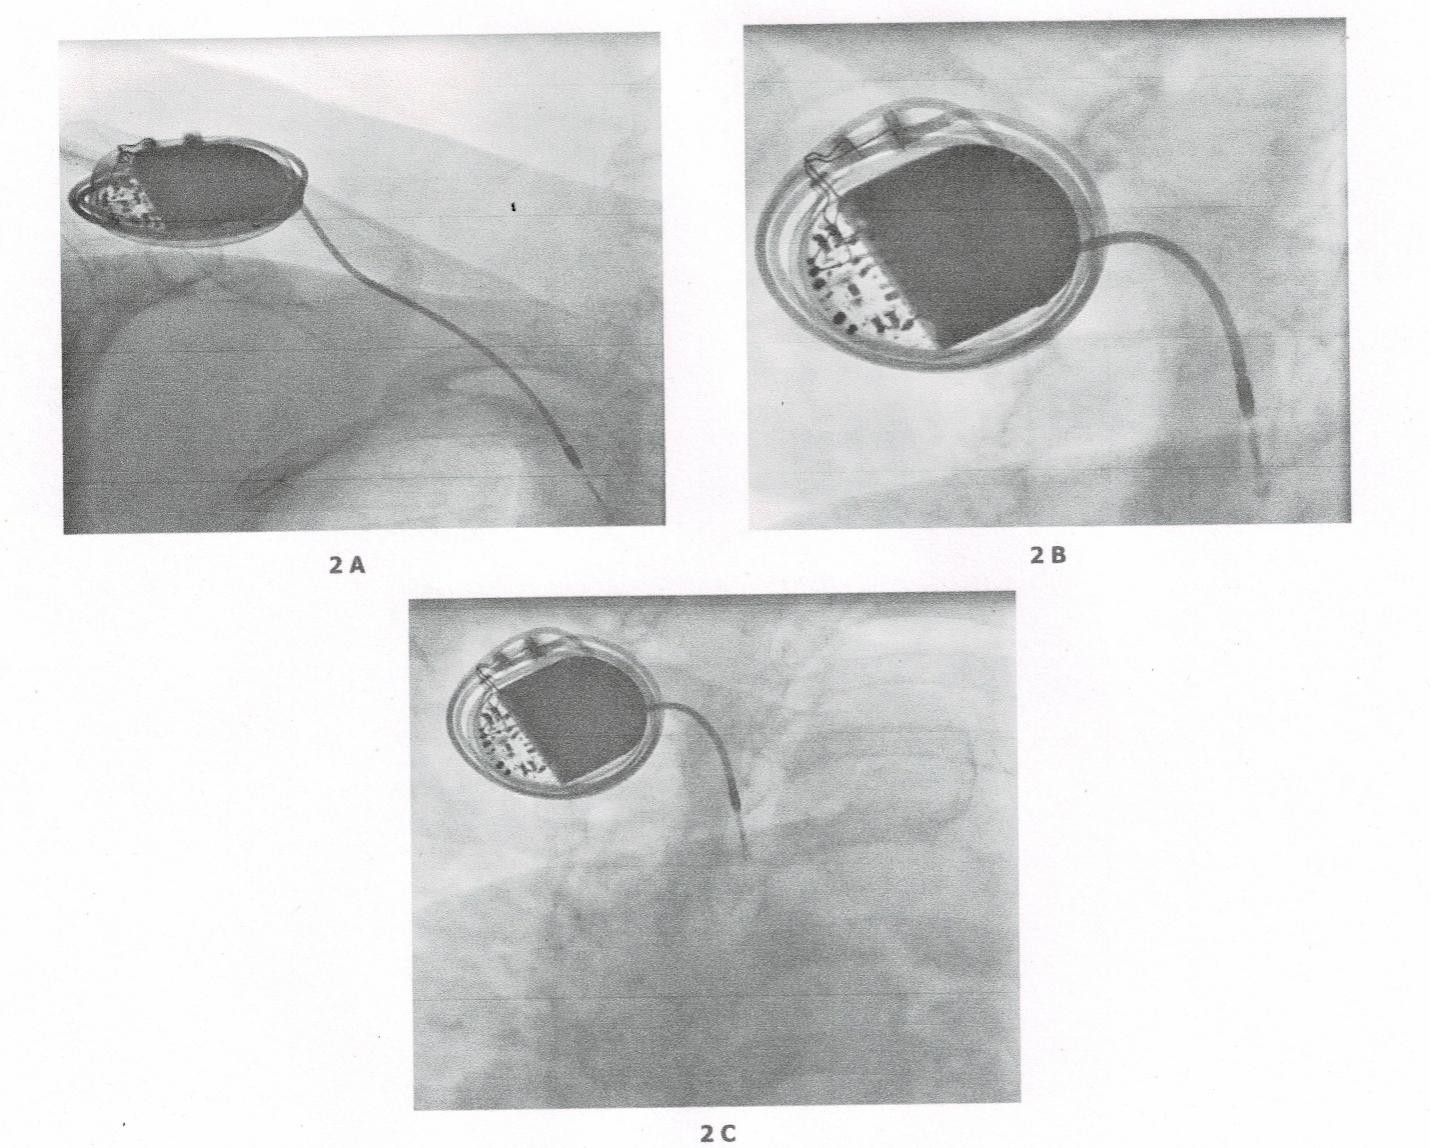

ECG at emergency department revealed loss of capture of pacemaker spikes [Figure 1]. Pacemaker interrogation showed complete loss of pacing and sensing of the ventricular lead. The patient admitted to any manipulation of the pace maker. Fluoroscopy revealed coiling of the pacing lead around the pulse generator [Figure 2]. The pacemaker pocket was reopened. Fortunately, both the insulation and the conductor of the lead were intact. The same lead was repositioned and proved to be functional with good pacing and sensing parameters [Figure 3]. The pulse generator was fixed on the pectoral muscle with non-absorbable sutures. No further complications were detected in one year follow-up.

Figure 2:

Details from a fluoroscopy showing the coiling of the pacing lead around the pulse generator of a pacemaker.

2A&2B: Pacemaker Defender Where both insolation and of the lead were intact.

2C&2D: The same lead was repositioned and proved to be functional with good pacing and sensing .